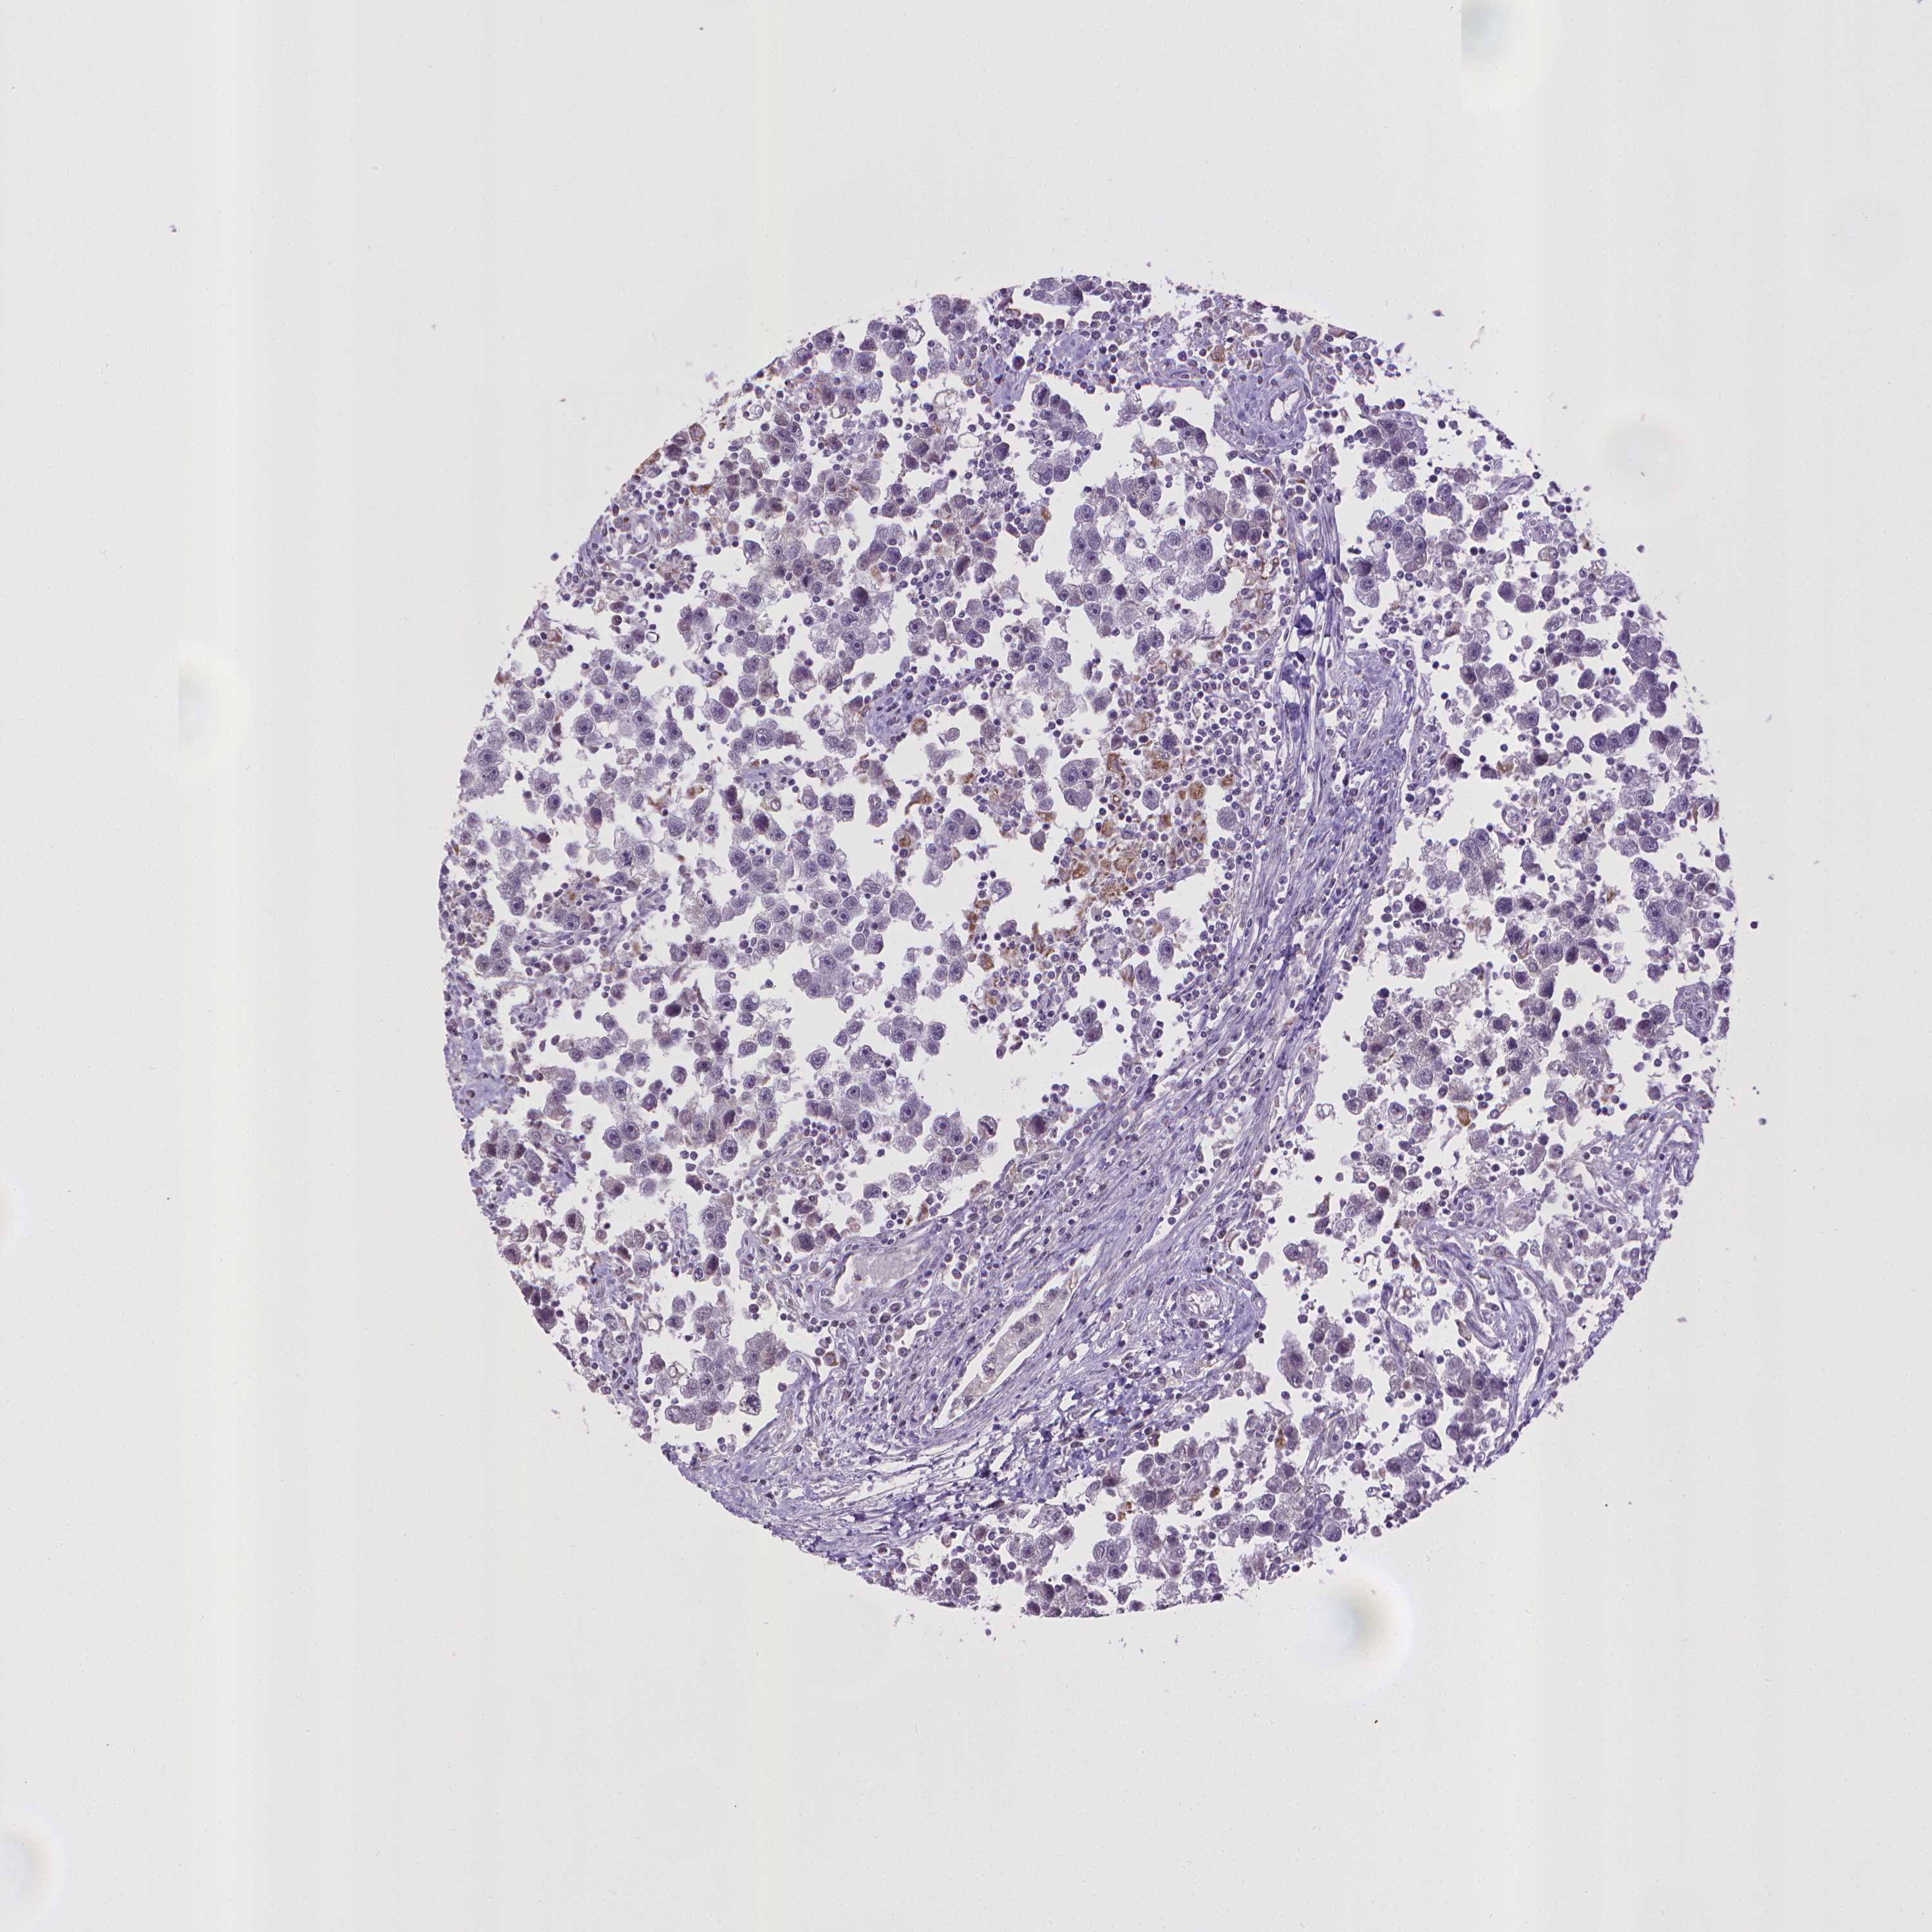

TESTIS CANCER - Protein expressioni

A mouse-over function shows sample information and annotation data. Click on an image to view it in a full screen mode. Samples can be filtered based on level of antibody staining by selecting one or several of the following categories: high, medium, low and not detected. The assay and annotation is described here.

Note that samples used for immunohistochemistry by the Human Protein Atlas do not correspond to samples in the TCGA dataset.

Antibody stainingi

Antibody staining in the annotated cell types in the current human tissue is reported as not detected, low, medium, or high, based on conventional immunohistochemistry profiling in selected tissues. This score is based on the combination of the staining intensity and fraction of stained cells.

Each image is clickable and will lead to virtual microscopy that enables deeper exploration of all samples and also displays staining intensity scores, fraction scores and subcellular localization as well as patient and tissue information for each sample.

Antibody HPA031115

Antibody HPA056942

Staining

High

Medium

Low

Not detected

Intensity

Strong

Moderate

Weak

Negative

Quantity

>75%

75%-25%

<25%

None

Location

Nuclear

Cytoplasmic/membranous

Cytoplasmic/membranous,nuclear

Seminoma, NOS

Carcinoma, Embryonal, NOS

Teratoma, malignant, NOS